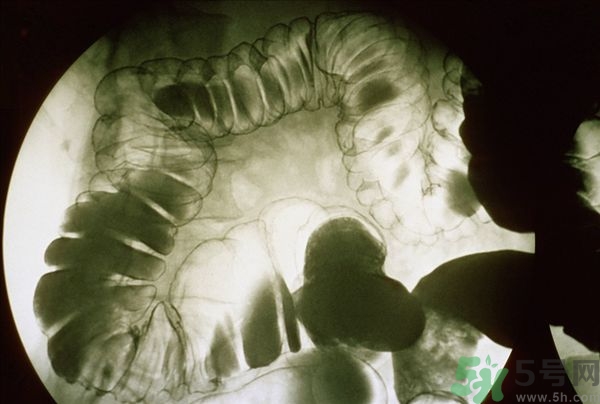

腸炎的分類其實(shí)有很多,比如盲腸炎、潰瘍性大腸炎、慢性腸炎、急性腸炎等等,是比較常發(fā)生的胃腸疾病,當(dāng)我們的腹部出現(xiàn)劇痛的時(shí)候首先我們要確定是哪一種疾病,并且要及時(shí)的進(jìn)行治療,腸炎嚴(yán)重的時(shí)候甚至有休克的可能,下面我們就來說說當(dāng)腸炎患者出一了腹前的時(shí)候應(yīng)該怎么緩解與治療。

腸炎的主要癥狀

(1)消化道癥狀

常呈現(xiàn)間斷性腹部隱痛、腹脹、腹痛、腹瀉為本病主要表現(xiàn)。遇冷、進(jìn)油(油食品)膩之物或遇情緒波動(dòng)、或勞累后尤著。大便次數(shù)增加,日行幾次或數(shù)十余次,肛門下墜,大便不爽。慢性腸炎急性發(fā)作時(shí),可見高熱、腹部絞痛、惡心嘔吐、大便急迫如水或粘凍血便。

(2)全身癥狀

呈慢性消耗癥狀,面色不華精神不振,少氣懶言,四肢乏力,喜溫怕冷。如在急性炎癥期,除發(fā)熱外,可見失水、酸中毒或休克出血表現(xiàn)。

(3)體征方面

長(zhǎng)期腹部不適或少腹部隱隱作痛,查體可見腹部、臍周或少腹部為主,有輕度壓痛、腸鳴音亢進(jìn)、脫肛。